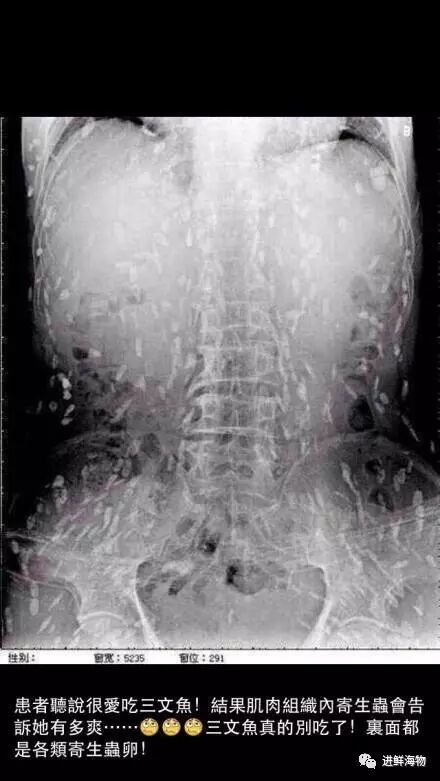

还有疯传的满是白斑的CT片都几乎变相坐实了生吃鱼片就是会得寄生虫病的“事实”。

就是这张吓怕很多人的照片……